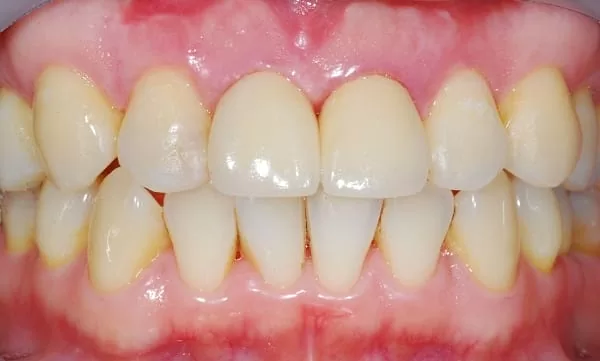

那天來先拆掉我門牙上面舊的牙套及釘子,採無創傷性拔牙將右上門牙拔除,並立即植牙,其骨質缺損的地方用骨粉及再生膜填補。三個月後以臨時牙套進行牙齦塑型,使兩顆門牙對稱並且能像原來牙齒般自然;經過一個月後,裝上植牙柱心,製作全瓷冠,完全看不出來曾經接受過植牙,總算不用再到處流浪找牙醫,也解決一直來的疼痛。

最後接上植牙柱心,製作全瓷冠,瞧! 完全看不出來曾經接受植牙吧。